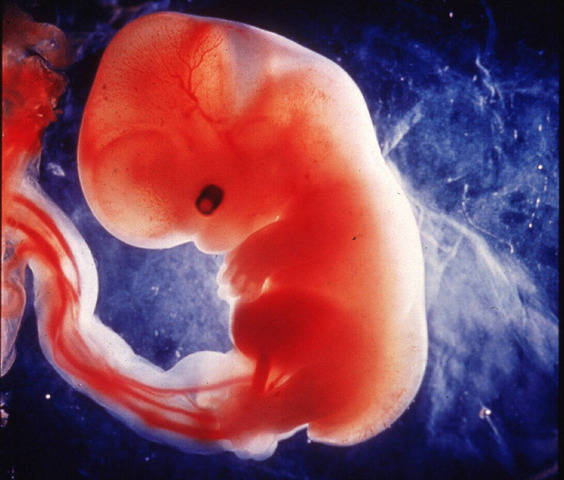

• DESARROLLO FETAL: SEMANA 4

DESARROLLO FETAL: SEMANA 4

En esta semana, se puede observar el tubo neural, bordeado por somitas, de donde surgirán la columna vertebral y las costillas. El corazón empieza a latir aunque sus cavidades no están totalmente desarrolladas.